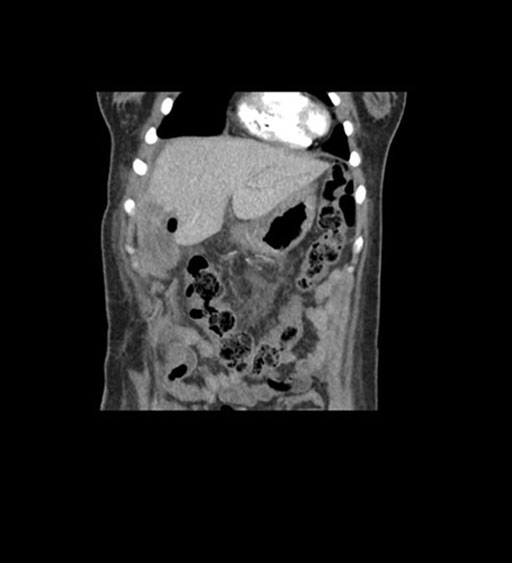

Coronal Arterial

Coronal Venous